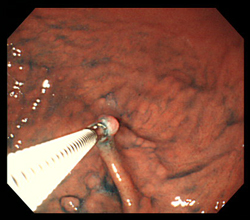

2. 내시경 중 조직 채취

의사는 내시경 카메라를 통해 위 내부를 관찰하면서 이상 부위를 발견하면, 내시경 끝에 부착된 작은 겸자(Forceps)를 이용해 점막의 일부를 매우 소량 떼어냅니다. 일반적으로 통증은 거의 없으며, 일부 환자는 ‘찌릿’한 느낌 정도만 느낄 수 있습니다. 한 번의 검사에서 2~5개 정도의 조직을 채취하는 것이 일반적입니다.